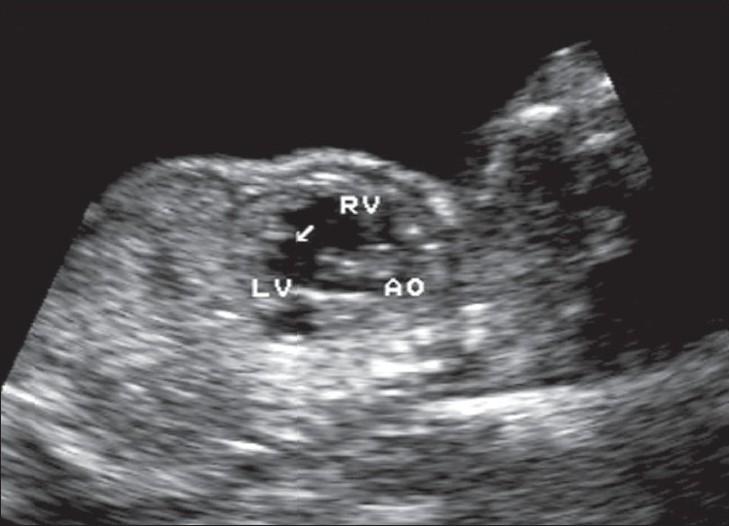

Absent pulmonary valve syndrome is a rare congenital anomaly, usually seen in association with a ventricular septal defect. It has been reported to occur in 3-6% of cases of tetralogy of Fallot. Absence of the pulmonary valve results in a dilated main pulmonary artery, which can be seen as a cystic, pulsatile, paracardiac lesion on antenatal USG. Such a lesion, though rare, can easily be detected. We report a case of this rare anomaly which was present in association with a ventricular septal defect, tetralogy of Fallot, and dextrocardia. The case was detected at 26 weeks of gestation.

肺动脉瓣缺如综合征是一种罕见的先天性畸形,通常与室间隔缺损相关。据报道,它在法洛四联症病例中发生率为3% - 6%。肺动脉瓣缺如会导致主肺动脉扩张,在产前超声检查中可表现为心脏旁的囊性、搏动性病变。这种病变虽然罕见,但很容易被检测到。我们报告了一例这种罕见畸形病例,该病例同时合并室间隔缺损、法洛四联症和右位心。该病例在妊娠26周时被检测到。